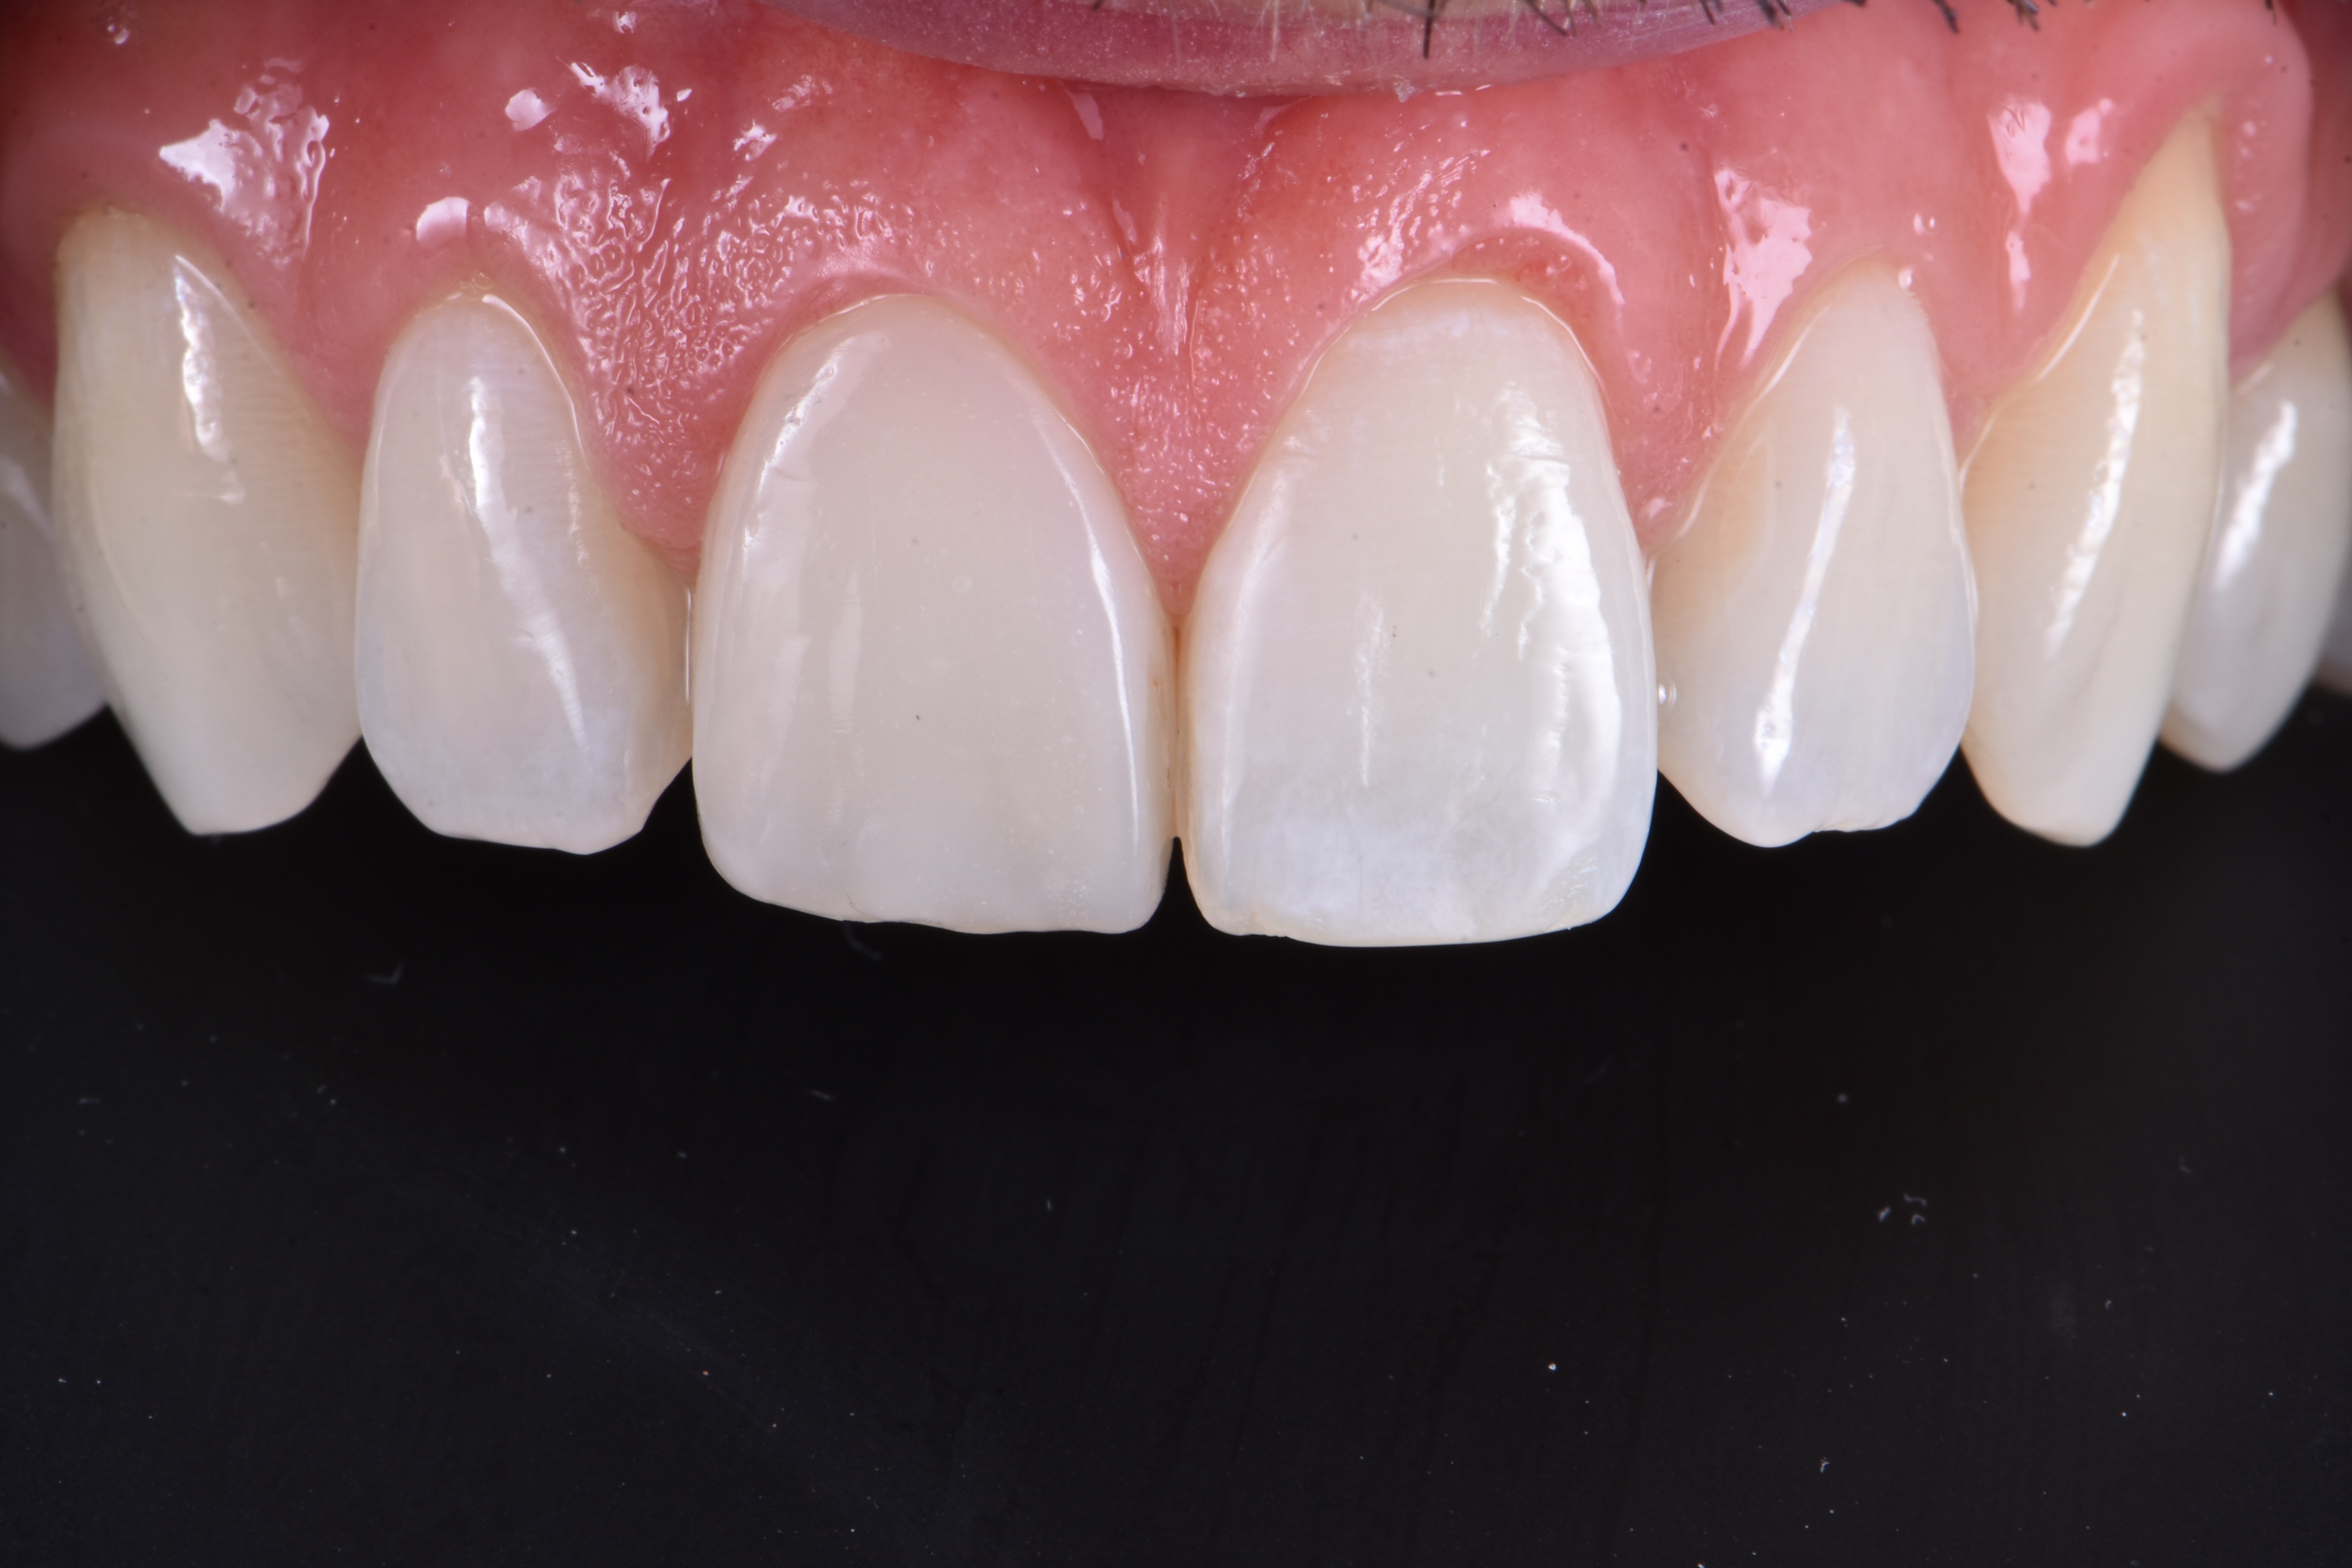

Odbudowę uzupełniono poprzez zastosowanie odcienia szkliwnego (ESTELITE ASTERIA WE firmy TOKUYAMA DENTAL) w postaci jednej warstwy. Powierzchnię przedsionkową wymodelowano i skontrolowano w każdym wymiarze, aby jak najmniej trzeba było ostatecznie korygować. Następnie spolimeryzowano w ciągu 20 sekund, a potem przez 40 sekund od strony przedsionkowej i podniebiennej po pokryciu żelem glicerynowym w celu uniknięcia powstania warstwy inhibicji tlenowej kompozytu (ryc. 11).